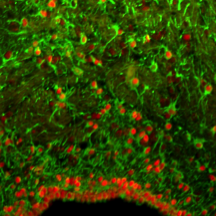

Neuroprotective Nanoparticles for treating CNS injuries: We began investigating the efficacy of unique neuroprotective nanoparticles in CNS injuries, particularly in stroke and spinal cord injury. We recently expanded my research into the area of blast wave-associated traumatic brain injury (bTBI), a significant issue for the military. Our overall therapeutic strategy is to inhibit the progression of the secondary injury cascades of degenerative events that follow the primary injury and promote the endogenous brain-repair mechanisms. Our recent and ongoing studies have demonstrated that delivery of neuroprotective nanoparticles at the time of reperfusion in a stroke model is effective in minimizing the damage due to ischemia/reperfusion injury, leading to neuronal regeneration and functional recovery over time. We are now expanding our research to other types of CNS injuries.

Petro M, Jaffer H, Yang J, Kabu S, Morris VB, Labhasetwar V. Tissue plasminogen activator followed by antioxidant-loaded nanoparticle delivery promotes activation/mobilization of progenitor cells in infarcted rat brain. Biomaterials. 2016 Mar;81:169-180.